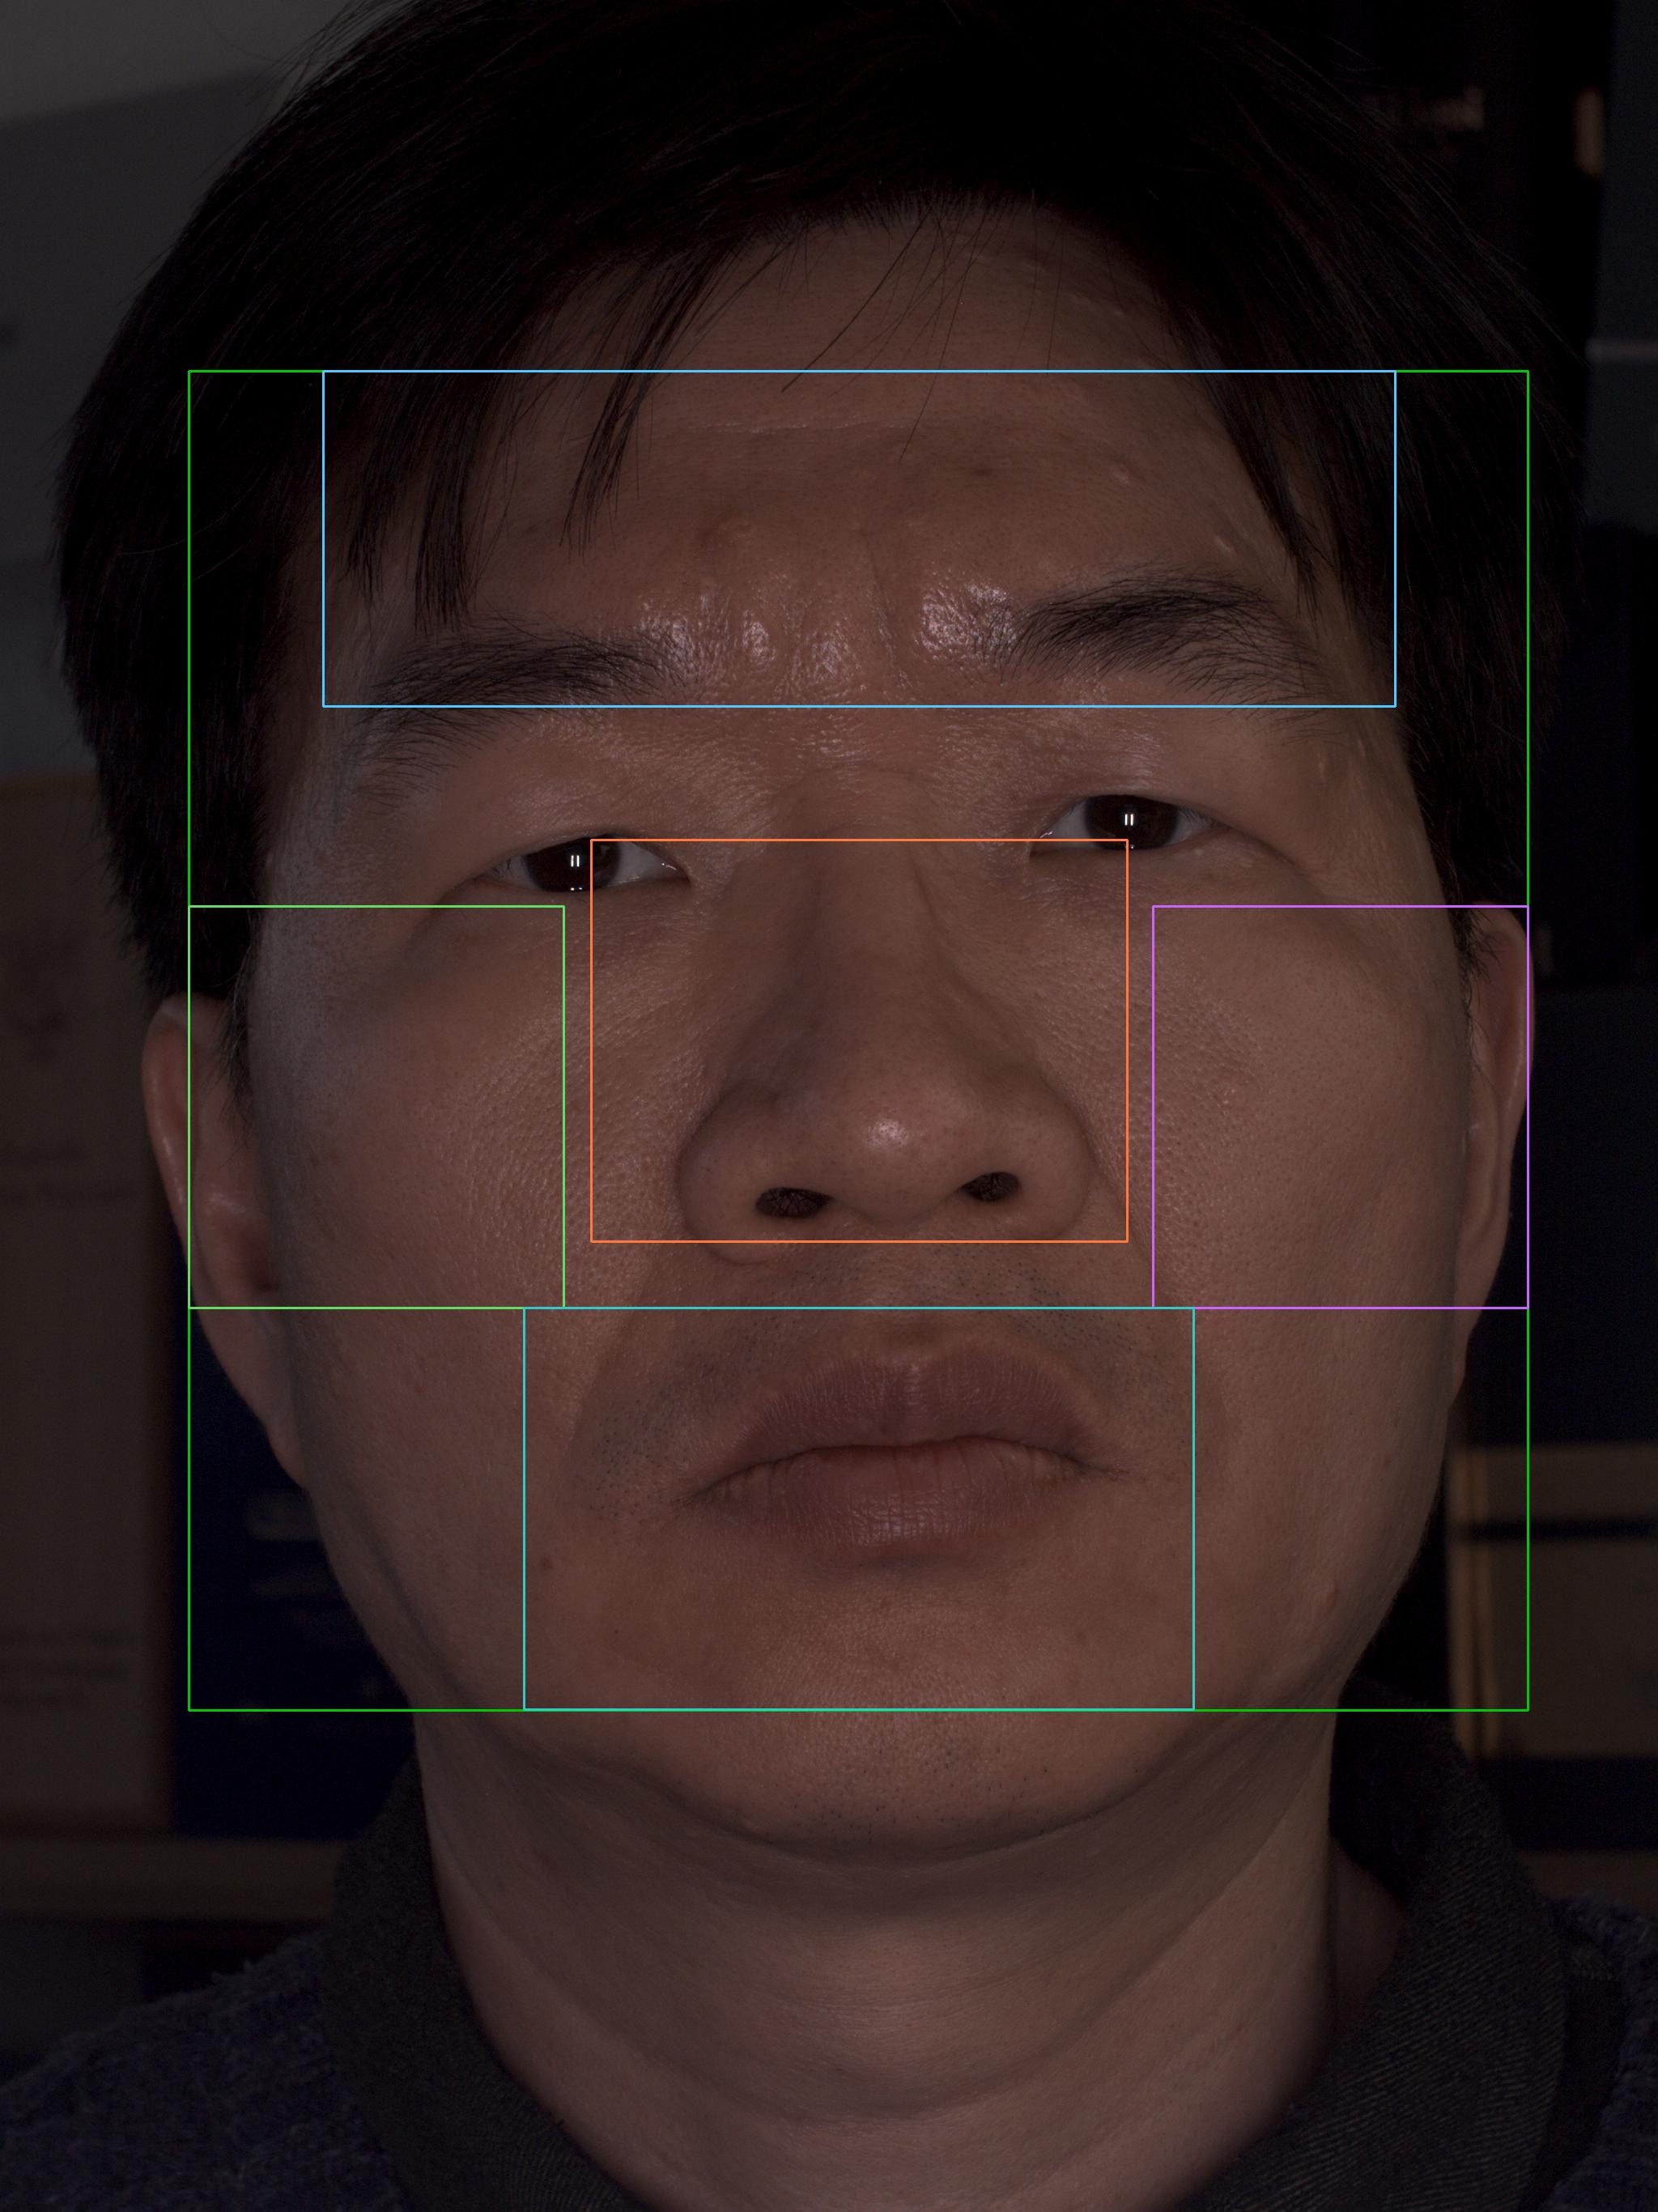

이마

유효 주름 수 4개 · 주 방향 가로

상위 깊이(평균 상위3) 0.320 mm

| # | 길이(mm) | 깊이(mm) | 유효 판정 근거 |

|---|---|---|---|

| 1 | 8.63 | 0.110 | 대표 깊이 0.110 mm가 이 부위 최소 깊이 0.100 mm 이상이고, 유효 길이 8.63 mm가 최소 길이 5.00 mm 이상이어서 노이즈·미세선과 구분되어 유효 주름으로 집계되었습니다. |

| 2 | 10.47 | 0.161 | 대표 깊이 0.161 mm가 이 부위 최소 깊이 0.100 mm 이상이고, 유효 길이 10.47 mm가 최소 길이 5.00 mm 이상이어서 노이즈·미세선과 구분되어 유효 주름으로 집계되었습니다. |

| 3 | 5.76 | 0.322 | 대표 깊이 0.322 mm가 이 부위 최소 깊이 0.100 mm 이상이고, 유효 길이 5.76 mm가 최소 길이 5.00 mm 이상이어서 노이즈·미세선과 구분되어 유효 주름으로 집계되었습니다. |

| 4 | 14.61 | 0.477 | 대표 깊이 0.477 mm가 이 부위 최소 깊이 0.100 mm 이상이고, 유효 길이 14.61 mm가 최소 길이 5.00 mm 이상이어서 노이즈·미세선과 구분되어 유효 주름으로 집계되었습니다. |